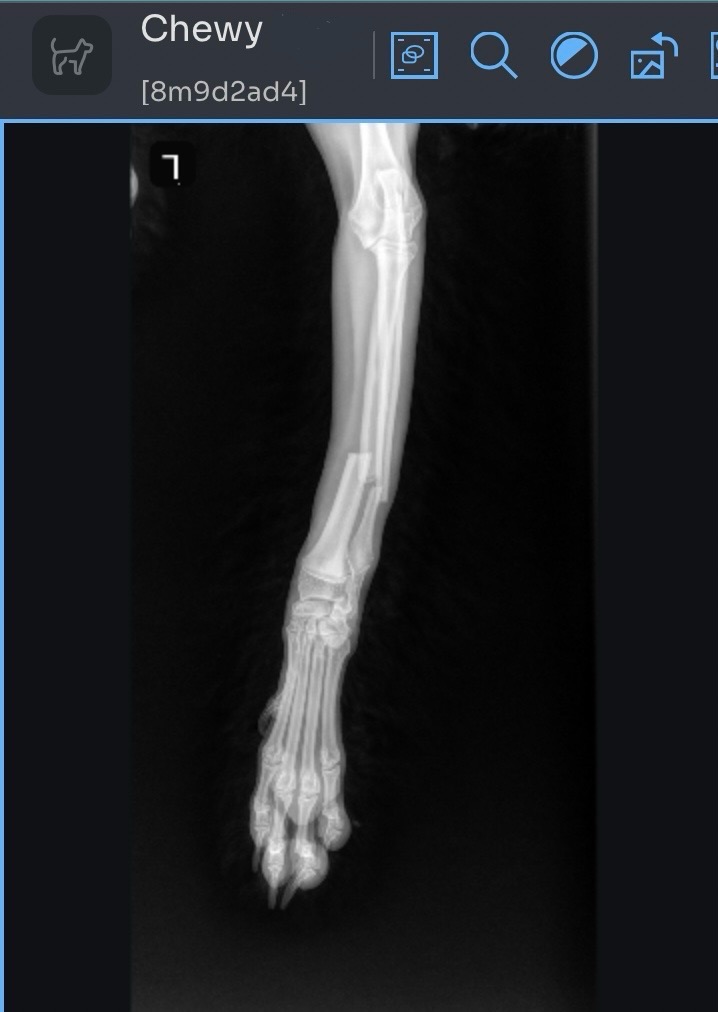

Chewy, my 7 month old puppy, broke two bones in his leg while playing at home over the weekend. After rushing to a late night ER Vet Visit, he is now having emergency surgery on 06/12/25 to have a titanium plate & up to 8 screws put in. His expected recovery is 12 weeks, requiring medicine, rest, and weekly vet visits for a fresh cast/splint.